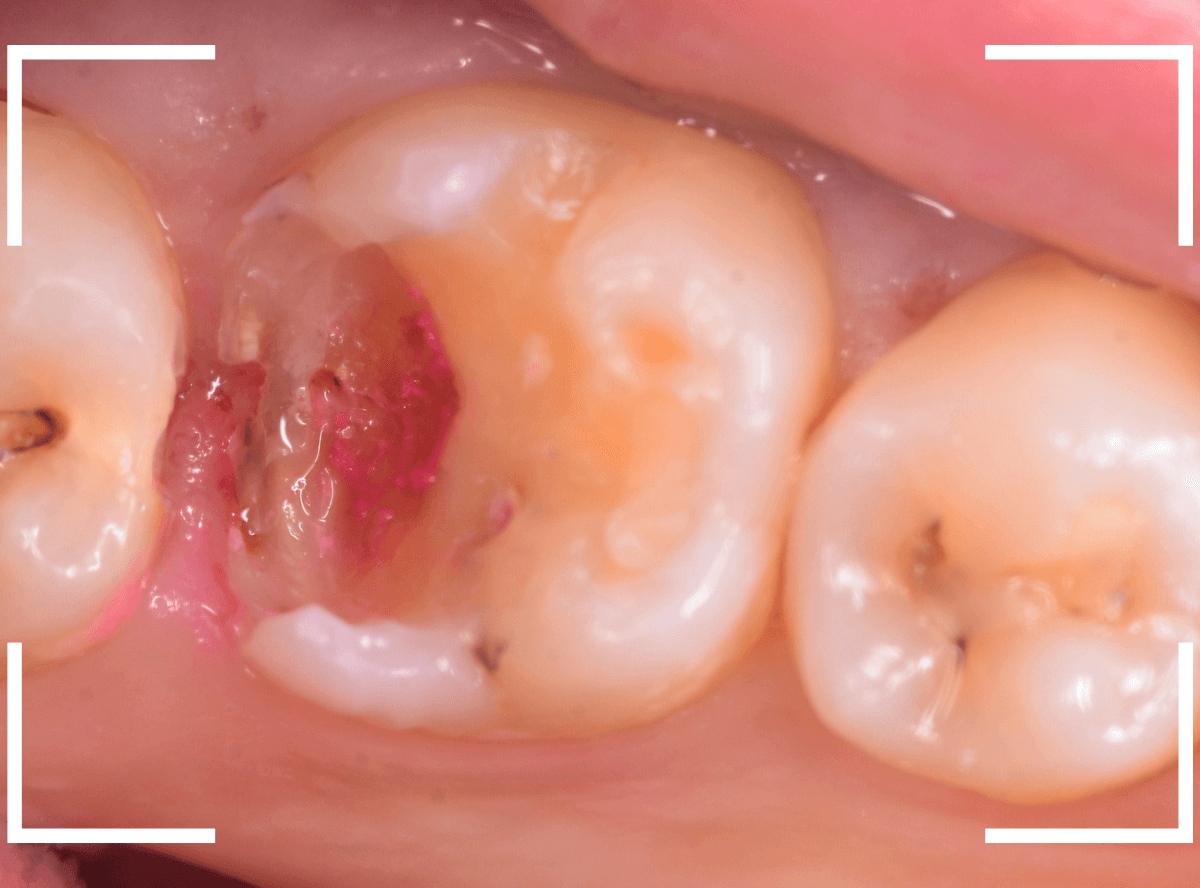

神経を除去する治療が必要かもしれないです。

全ての虫歯を除去したところです。

幸い、後ろの歯は薄皮一枚のところで神経まで達していない虫歯ですんでいましたが、大きな虫歯だった事には変わりありません。

いつものように、神経が痛み出さないように祈りつつ、お薬で保護して経過観察します。